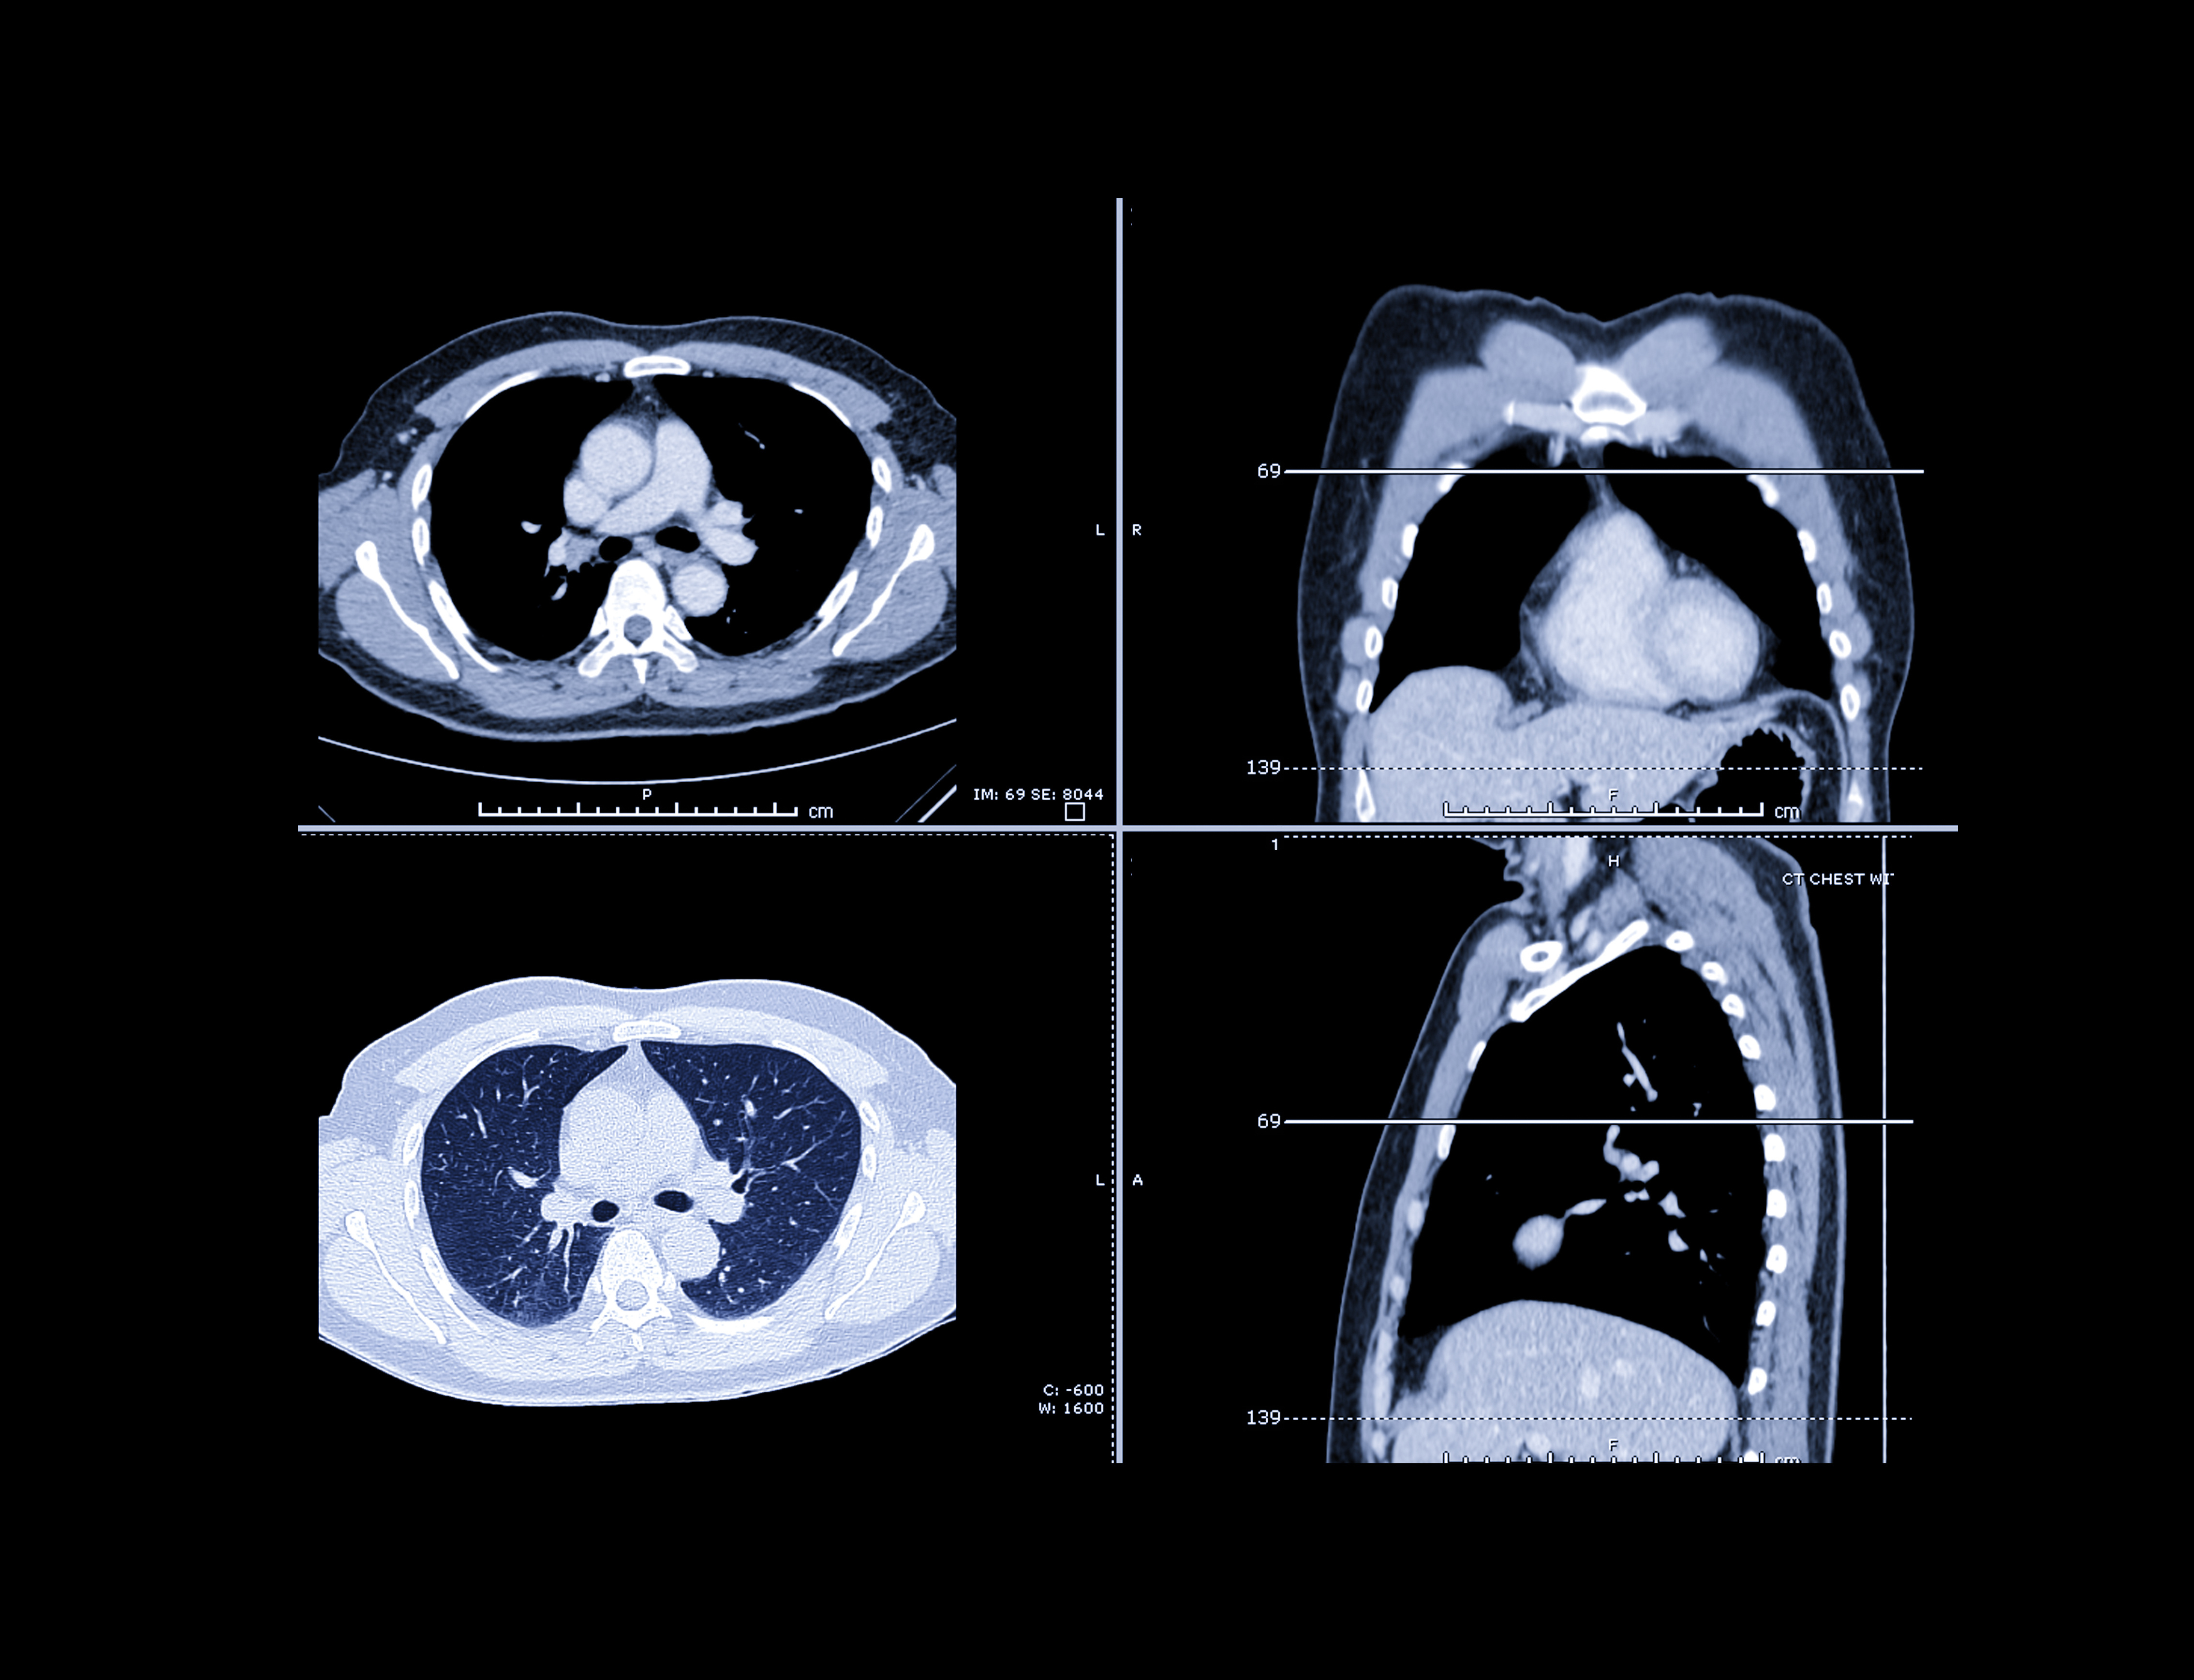

This poster presentation will describe how deep learning may offer assistance in the challenging task of identifying interstitial lung disease.Identifying patterns of interstitial lung disease (ILD) can be challenging due to the large variation of disease appearance, location, and configuration, according to co-author Ziyue Xu, PhD, of the U.S. National Institutes of Health (NIH) Clinical Center. This task is typically handled by expert radiologists and is very time-consuming; interstitial lung diseases can cover a large portion of the lung, with different patterns coexisting on a single CT slice.

To address these challenges, the NIH team developed a convolutional neural network that is designed to simultaneously detect multiple patterns of interstitial lung disease from a CT slice. It also utilizes the entire CT slice as an input, obviating the need to manually draw a region of interest for the software to analyze.